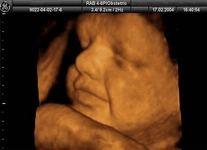

23 haftalık gebelik, hamileliğin ikinci trimesterinin sonlarına yaklaşıldığı bir dönemi ifade eder. Bu süre zarfında, hem anne hem de bebek için birçok önemli gelişim ve değişiklik yaşanmaktadır. Bu makalede, 23 haftalık gebelik dönemindeki fiziksel ve duygusal değişimlerin yanı sıra, bebeğin gelişimi, anne adayının sağlığı ve dikkat edilmesi gereken hususlar ele alınacaktır. Bebeğin Gelişimi23 haftalık gebelikte bebek, hızla büyümeye devam etmekte ve birçok önemli gelişim sürecinden geçmektedir. Bu dönemde, bebeğin gelişimiyle ilgili bazı önemli noktalar şunlardır: